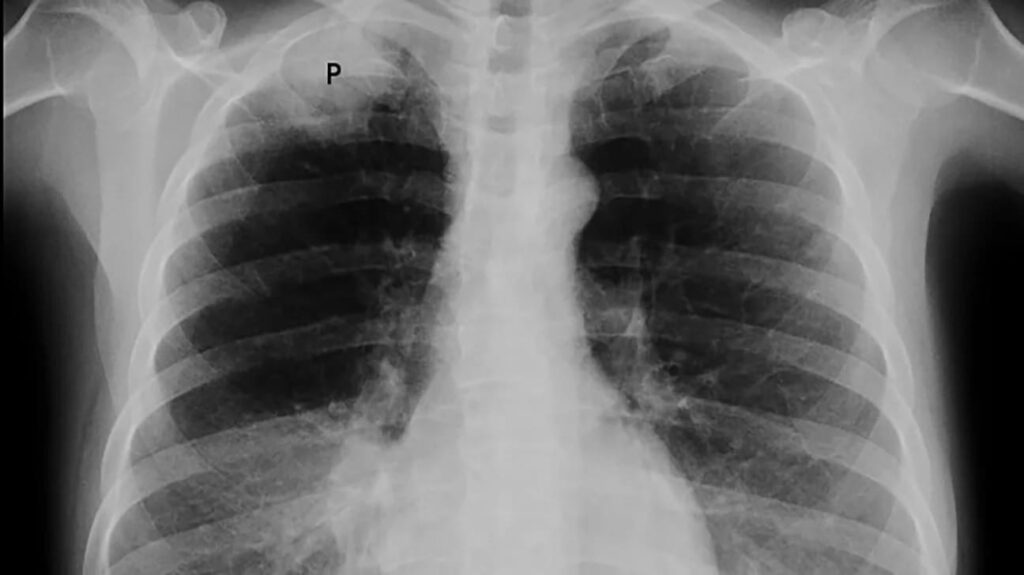

Caverna tuberculosa

Pedro Chaparro Mutiz, MD, Juvenal Baena, MD**. *Internista Neumólogo.Jefe Servicio de Broncoscopia-Hospital Santa Clara,Bogotá ** Profesor de Neumologia-Universidad El Bosque....